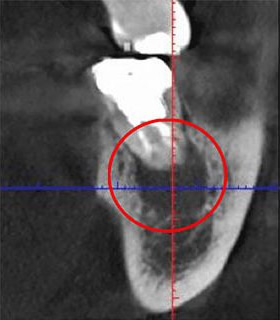

以下は、同じ歯をCTとレントゲンで撮影した画像の比較です。

• 画像

CT画像

レントゲン画像

左の写真では黒い影が見えますが、右の写真にはありません。実はこの黒い影が、歯の根の炎症です。

つまりレントゲン検査だけだと炎症を発見できず、見逃してしまう可能性があるということです。CTを使うことで、初期の炎症も見逃すことなく、適切な診断ができます